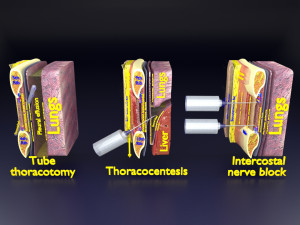

A blend model of brain along with its covering layers (meninges), skull bone and scalp labelled in detail and anatomically precise. The parts depicted are white, gray, pia, arachnoid, dura, bone, skin, fat, aponeurosis, periosteum, falx cerebri and more.